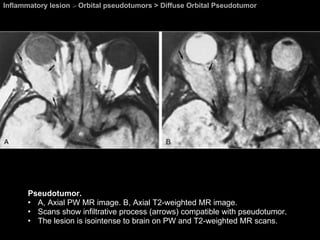

Diffuse Orbital Pseudotumor Orbital pseudotumors  Tumefactive, or infiltrative type of pseudotumor Entire retrobulbar space and mold itself around the globe while respecting its natural shape.  These large, bulky masses can be intraconal, extraconal, or involve both spaces.  Very difficult to differentiate from lymphoma.

Inflammatory lesion  >  Orbital pseudotumors > Diffuse Orbital Pseudotumor Pseudotumor. Axial CT scan shows diffuse infiltration of the entire retrobulbar space. The optic nerve appears as a lucent band (arrow) embedded within the lesion.

Inflammatory lesion  >  Orbital pseudotumors > Diffuse Orbital Pseudotumor Pseudotumor. A, Axial PW MR image. B, Axial T2-weighted MR image.  Scans show infiltrative process (arrows) compatible with pseudotumor.  The lesion is isointense to brain on PW and T2-weighted MR scans.